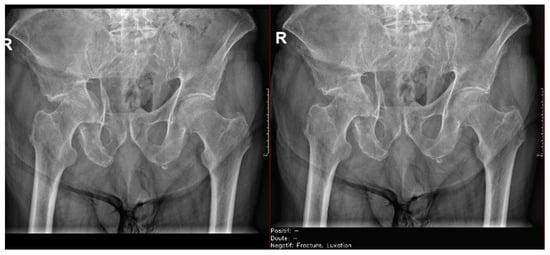

- Ankle and foot: On six occasions, Milvue marked the fracture variable as doubtful in cases with a bipartite medial sesamoid (two patients), an accessory sesamoid at the base of the 5th metatarsal, synphalangism, os peroneum, and os naviculare. (Figure 8).

- Hand: Milvue marked the fracture variable as doubtful in the case of multiple accessory ossicles.

- Wrist: On four occasions, Milvue marked the fracture variable as doubtful in cases of os paranaviculare, os trapezium secundarium, os ulnar styloid, and os paratrapezium. However, Milvue did not detect fractures in three cases of os ulnar styloid, two cases of accessory ulnar styloid, nor in cases of os hypolunatum and os epilunatum.